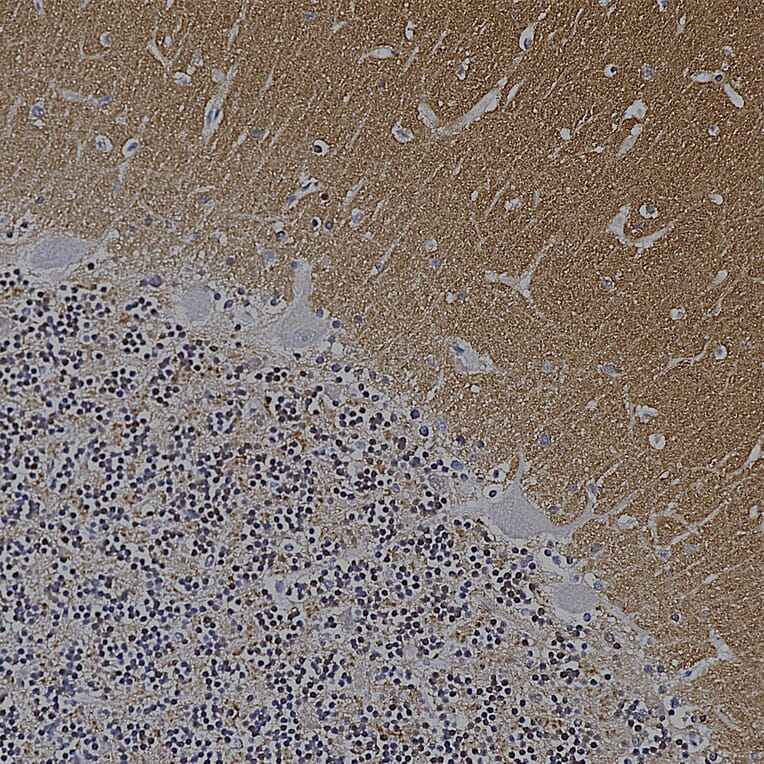

Immunohistochemistry analysis of a NBF fixed paraffin embedded human cerebellum section with Anti-alpha Synuclein Antibody [2A7] (A85290) at a dilution of 1:1,000 detected in DAB (brown) using the Vector Labs ImmPRESS method and reagents with citra buffer retrieval. Counterstained with Hematoxylin (blue). The a-synuclein antibody synaptic regions in the granular and molecular layers of the cerebellum. Note: this antibody performs well in testing with both 4% PFA and standard NBF fixed tissues.